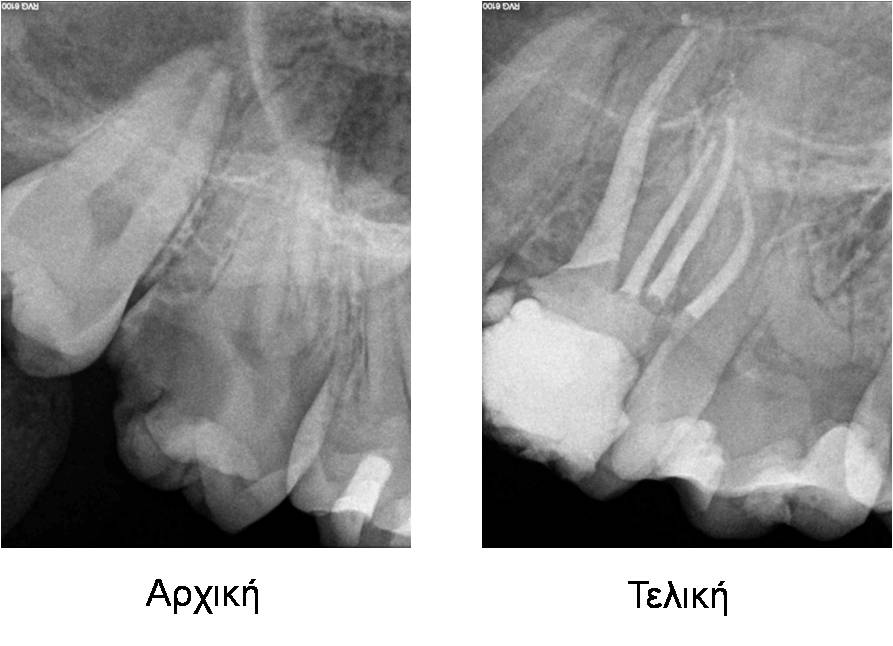

Περιστατικό 1

Αρχική ενδοδοντική θεραπεία

Περιστατικό 2

Αφαίρεση κώνων αργύρου